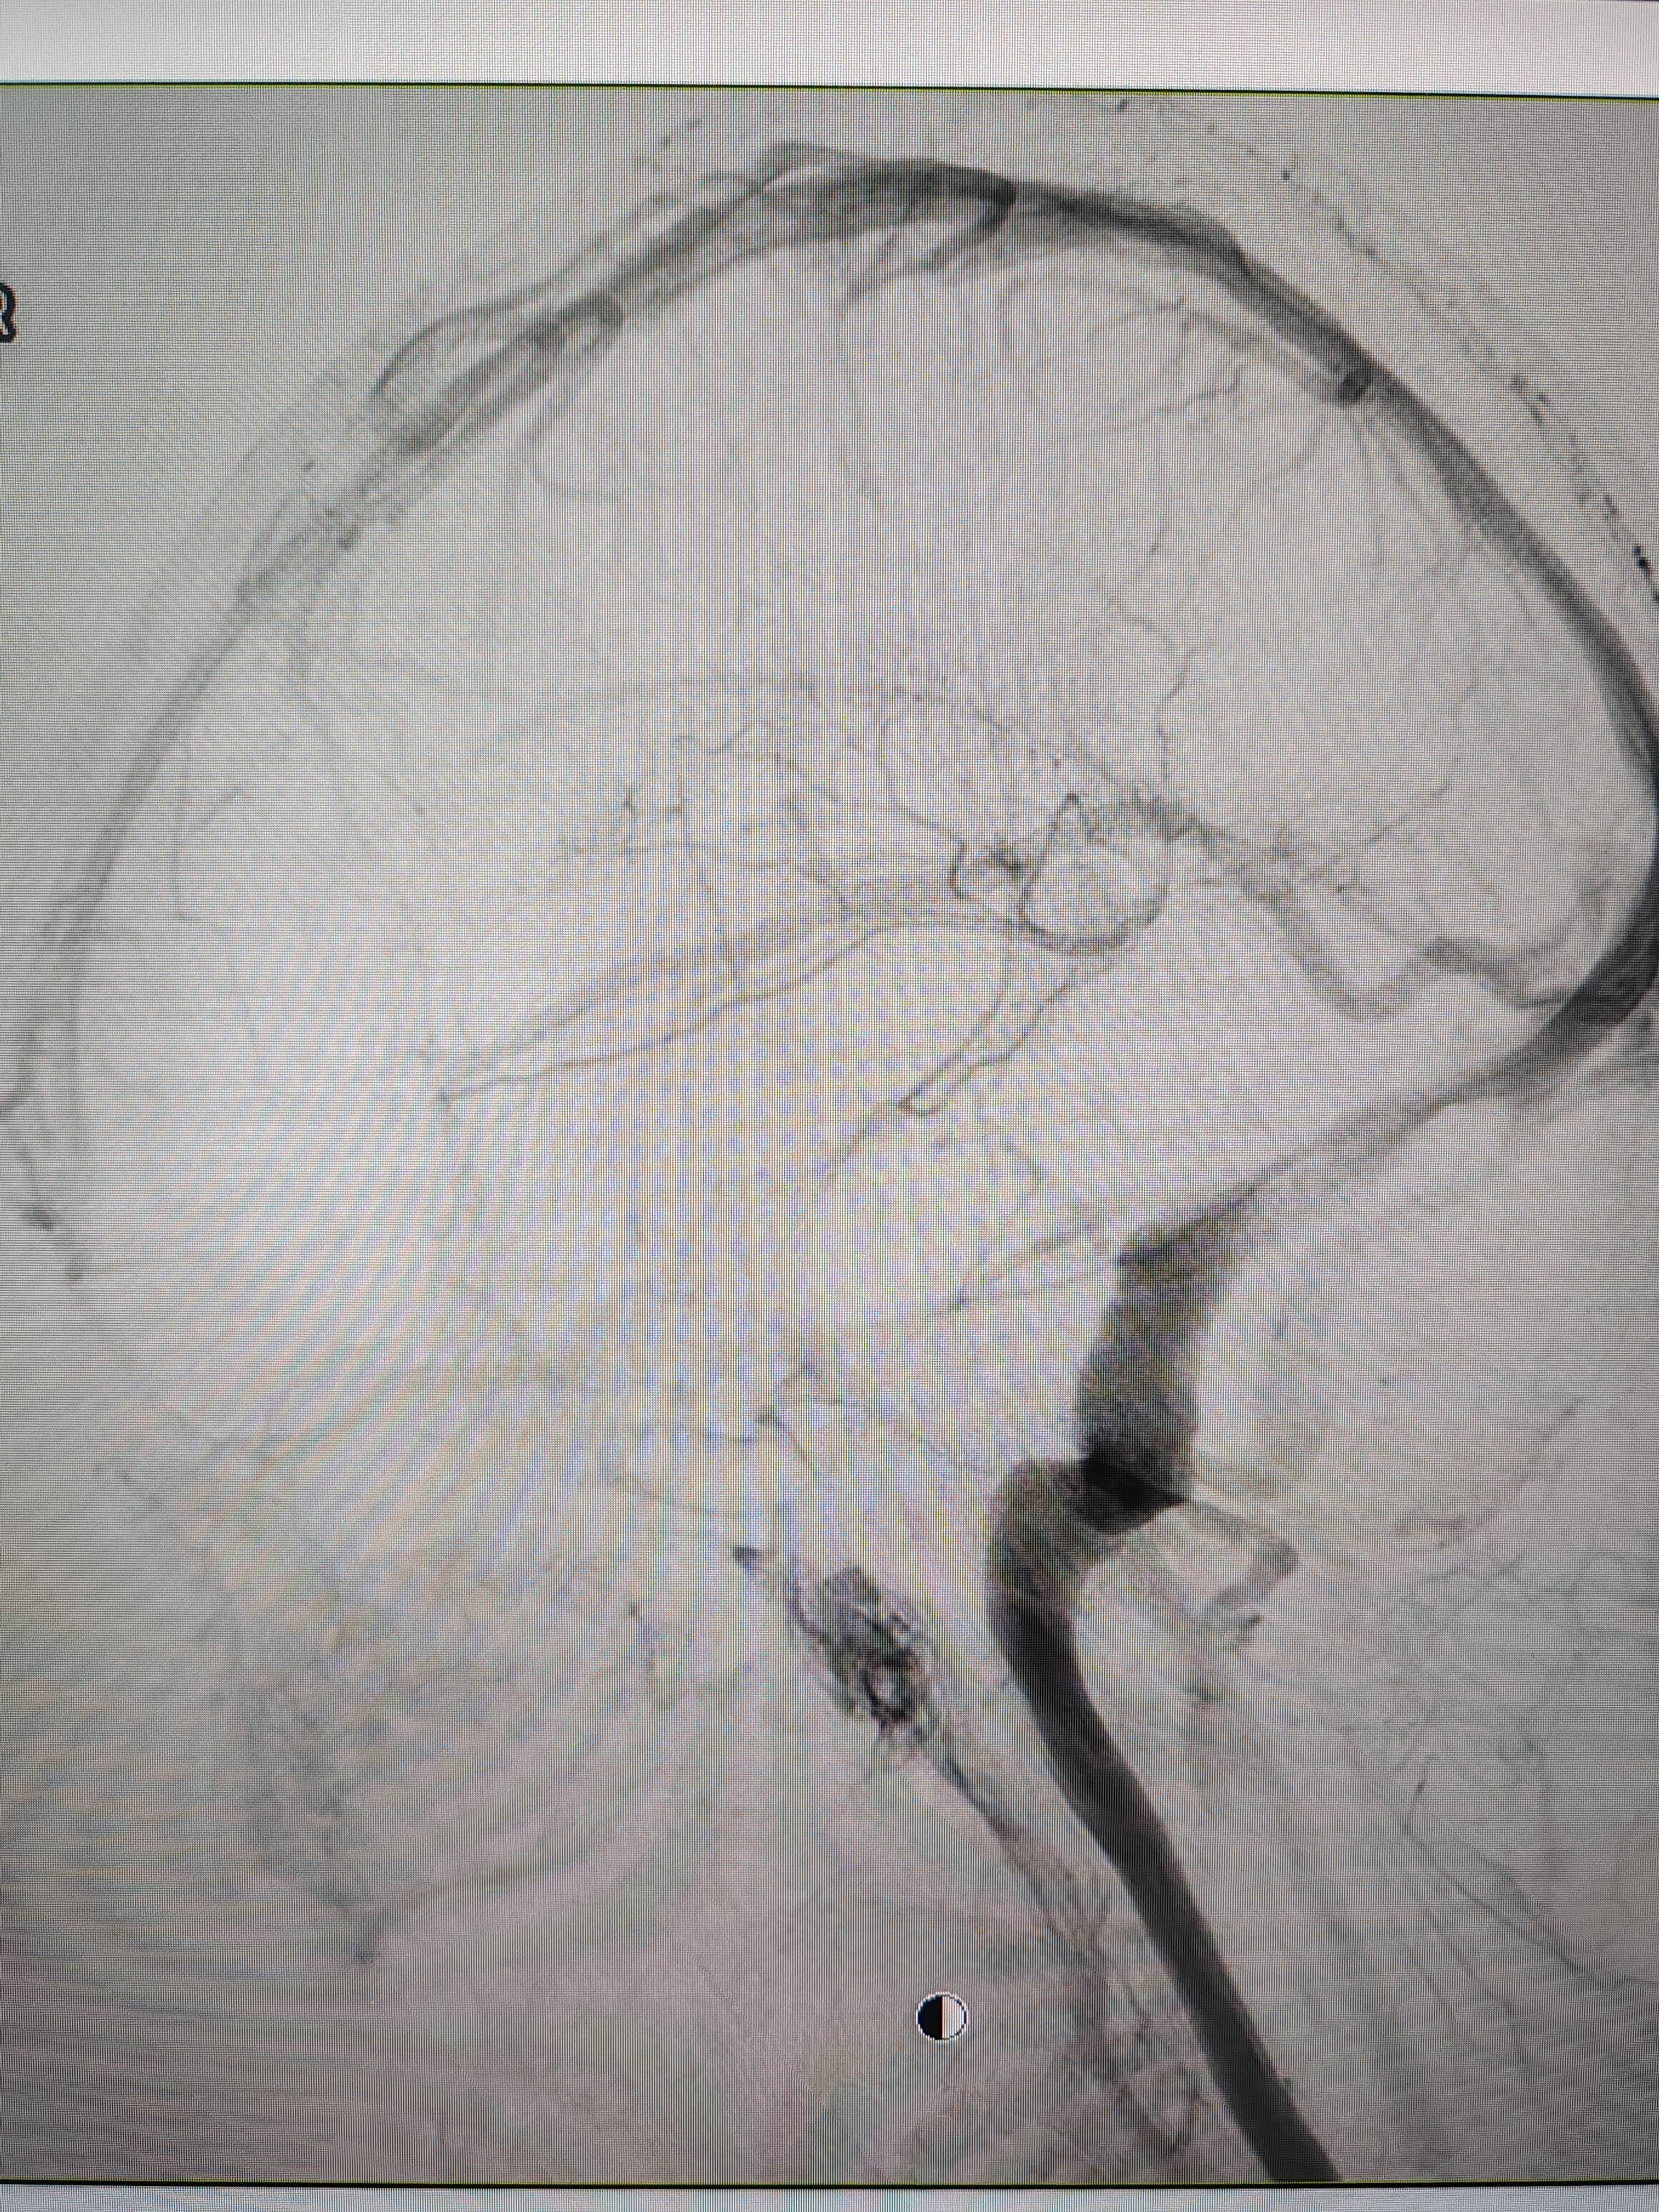

患者造影图像显示,其耳侧静脉窦狭窄p2p理财雷。 南方+ 欧阳少伟 拍摄

李宝民举例说,通过查体、CT、造影等影像技术的检查,患者赵女士是由于静脉窦狭窄,导致缓慢的静脉血流也出现“湍流”现象,其拐弯、打漩涡、回流产生的声响,又顺着骨传导,传至耳蜗处,进而让患者出现搏动性耳鸣的症状p2p理财雷。